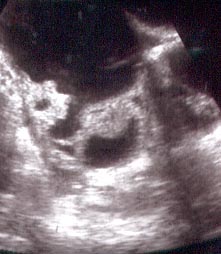

Photo Three

12 weeks fetus

This is a twelve weeks pregnancy as seen by external (through the abdomen) sonar.